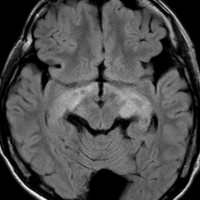

生後7カ月の幼児です。目が揺れるようになり(振り子様眼振)眼科を受診して腫瘍が発見されました。小児脳腫瘍の治療ができる病院へと紹介されました。

1ヶ月後にまたMRI検査がされました。乳児ですから検査にも麻酔が必要です。腫瘍は明らかに大きくなっています。左視神経から視索の腫瘍化が著しいので右側だけかすかに視力が残っているかもしれません。視力は明かりがわかる程度(明暗弁)と評価されました。